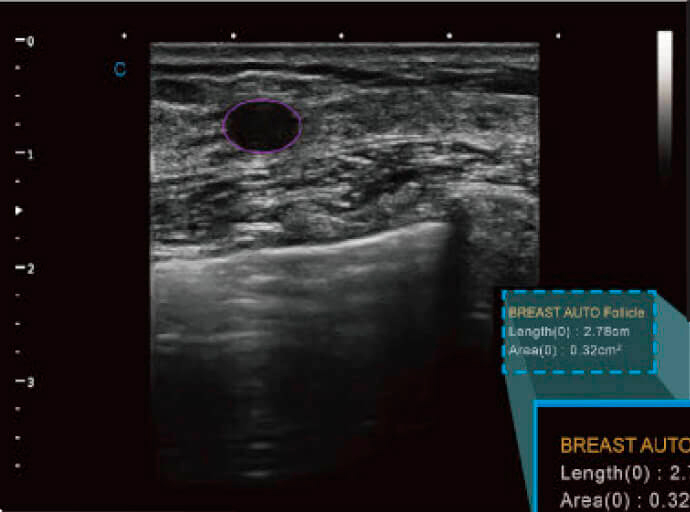

Détection automatique des blessures mammaires

- Détecte automatiquement les blessures au sein.

- Calculer la taille et l'étendue de la blessure.

- Fonction de diagnostic très efficace.

Détection automatique des follicules

- Quantifier le nombre de follicules et indiquer leur taille individuelle.

- Il devient un outil qui facilite la fluidité au travail.

- Parvient à guider le professionnel vers le traitement le plus précis et le plus précis.